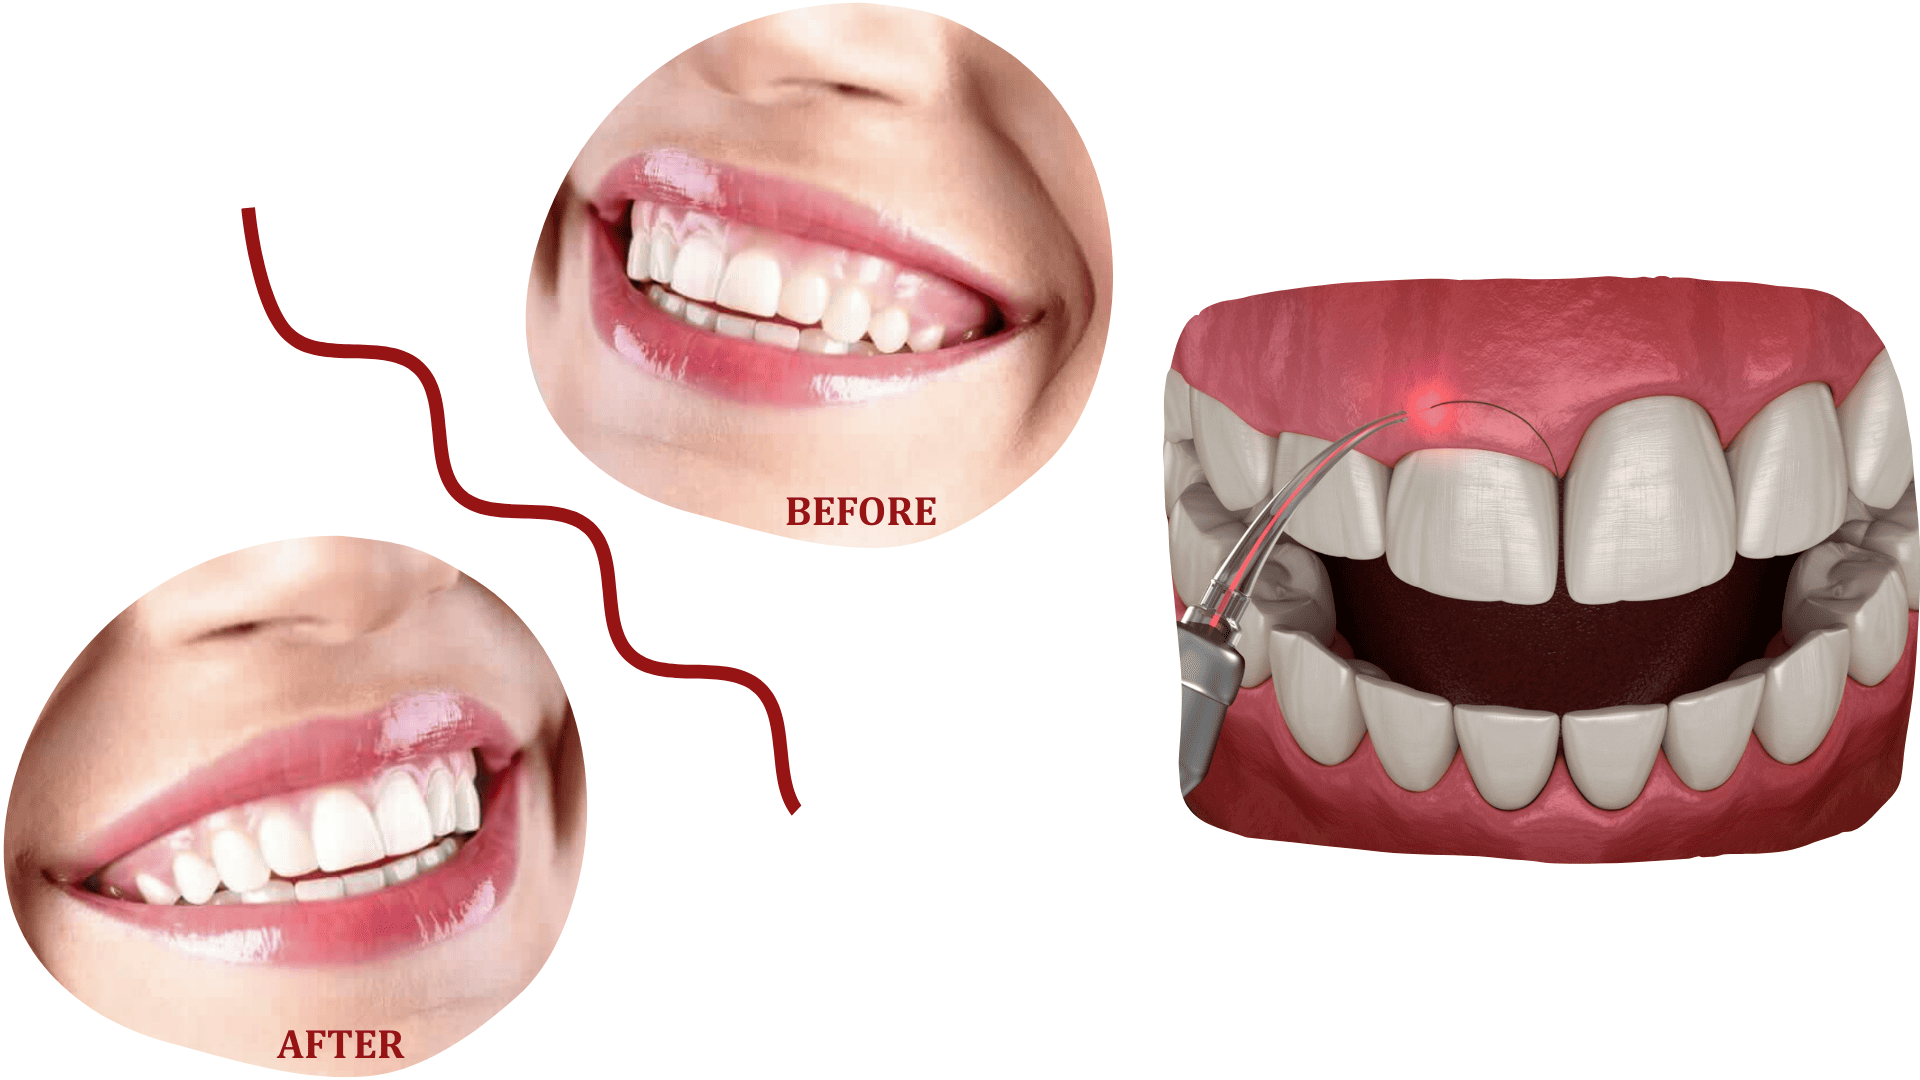

GINGIVEKTOMIJA

Gingivektomija je zahvat kojim se uklanja višak zubnog mesa (gingive), i to iz zdravstvenih ili estetskih razloga.

Izvodi se kod pacijenata s parodontalnim bolestima i upalama zubnog mesa, kao i kod onih kojima je potrebno ukloniti višak desni radi estetske korekcije osmijeha.

Zahvat se radi pod lokalnom anestezijom, a oporavak je brz i bezbolan.